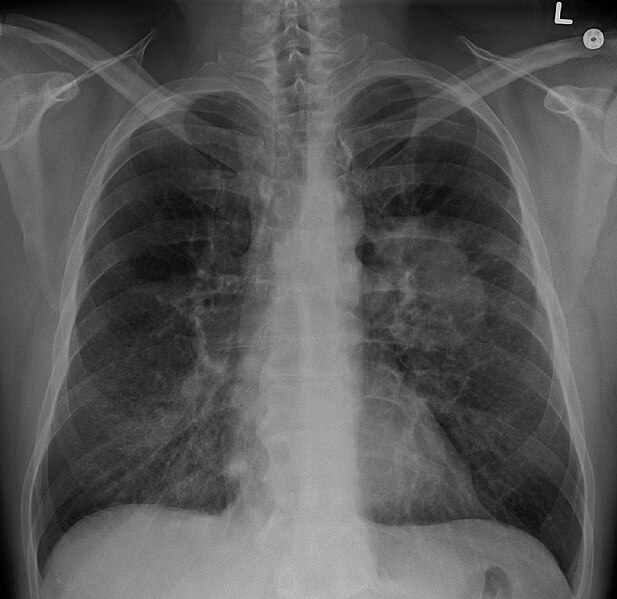

13

Q

what does this CXR show?

A

simple pneumothorax

- visible rim of air between lung margin + chest wall

- no visible lung markings